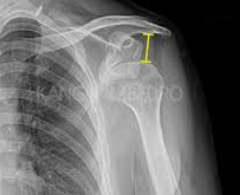

어깨탈구 원인

어깨탈구는 어깨 관절이 정상적인 위치에서 벗어나는 상태를 말합니다. 이는 어깨 관절을 구성하는 뼈, 근육, 인대, 힘줄 등이 손상되거나 약화됨으로써 발생할 수 있습니다. 어깨탈구의 가장 흔한 원인은 외상입니다. 넘어지거나 직접적인 충격을 받았을 때 어깨 관절이 강제로 움직이면서 탈구될 수 있습니다. 스포츠 활동 중에도 비슷한 상황이 발생할 수 있으며, 특히 충돌이나 반복적인 오버헤드 동작을 하는 스포츠에서 더 자주 보입니다.

또 다른 원인은 관절의 과도한 유연성이나 약화된 어깨 근육으로 인한 것일 수 있습니다. 이러한 경우, 갑작스러운 움직임이나 무리한 자세로 인해 탈구가 발생할 수 있습니다. 또한, 어깨 관절의 해부학적 구조상의 문제나 이전의 탈구 경험이 재발의 위험을 증가시킬 수 있습니다.

어깨탈구는 심한 통증과 함께 어깨의 움직임이 제한되는 것이 특징입니다. 탈구된 어깨는 의료 전문가에 의해 적절한 치료를 받아야 하며, 때로는 수술이 필요할 수도 있습니다. 예방을 위해서는 적절한 스트레칭과 강화 운동을 통해 어깨 근육을 튼튼하게 유지하는 것이 중요합니다. 또한, 위험한 활동을 할 때는 보호 장비를 착용하고, 안전 수칙을 준수하는 것이 좋습니다.